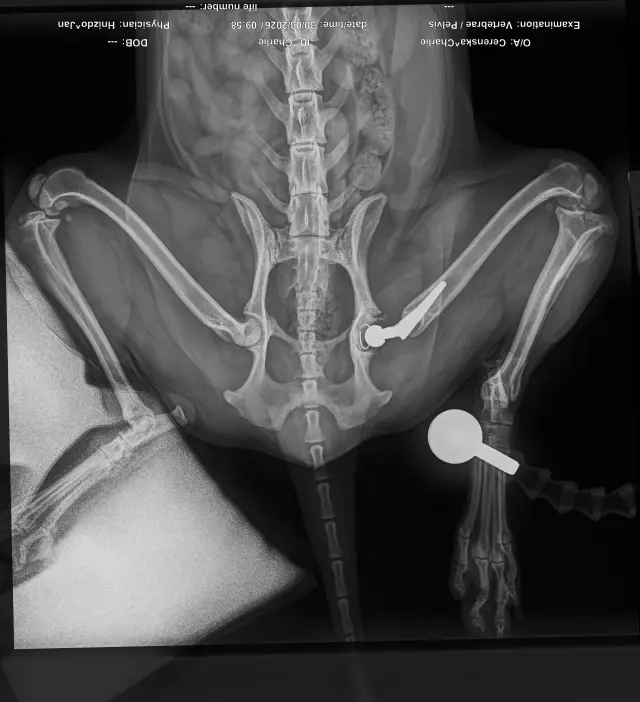

Sbírka je pro aktivního pejska Charlieho (Káju), který v říjnu 2025 podstoupil operaci cementované endoprotézy levé kyčle kvůli degenerativní coxartzróze. Samotná operace bez předoperačních a pooperačních kontrol vyšla na 64tis. Po dlouhé rekonvalescenci se opět vracel k normálnímu životu. Začalo se opět chodit na procházky, zatím ne žádné túry a vypadalo to, že vše bude v pořádku. Kontroly dopadli dobře, Charlie chodil i radostně pobíhal bez potíží. Už jsme si mysleli, že konečně bude mít klid od bolesti, ale bohužel začal náhle kulhat a chodit zadní částí těla do pravého boku. ❤️‍🩹

Nechali jsme tedy na veterině udělat orientační RTG snímky, bez přítomnosti ortopeda, byla již vidět luxace implantátu, proto jsme i během víkendu zkontaktovali MVDr. Jana Hnízda, který ho operoval a hned nás následující den pozval na RTG v sedaci. Bylo tedy zjištěno, že cement, který pojí umělou jamku s kostí se uvolnil a celý implantát jde tak v určitém pohybu do subluxace. 😥

Dorazili nám dnešní snímky, už ortopedicky přesnější